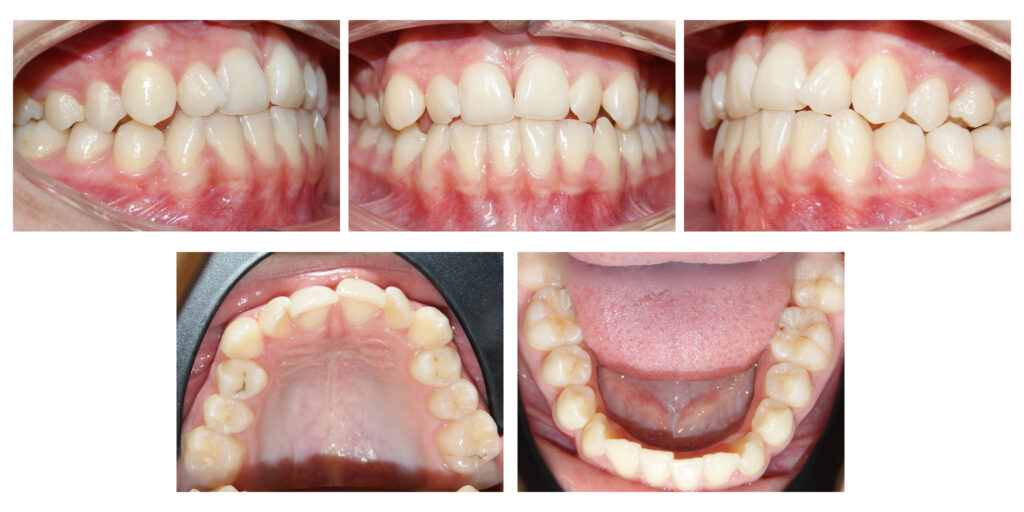

În cazul de față ortodonția ne-a ajutat să oferim lărgime semnificativă zâmbetului și să prevenim retracțiile gingivale de pe caninii inferiori prin distalizare.

Pentru că detaliile fac diferența  – a se remarca înălțarea și lărgirea zâmbetului #contenție fixă